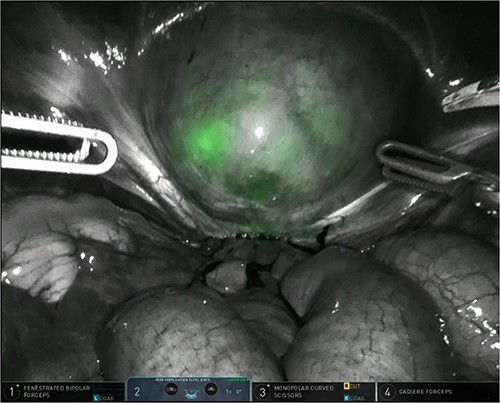

The patient was planned for a robotic resection of the endometriosis nodule and hysterectomy by an experienced robotic gynecological surgeon. The patient was placed on a PinkPad (Kebomed Europe AG) in a lithotomy position. Cystoscopy was performed with placement of ureteral stents. Double-J stents were guided up to the kidneys. Instillation of 200 ml physiologic water with 2 cc of ICG (1.9 mg/cc) in an empty bladder, with subsequent clamping of the urinary catheter (Fig. 3). The da Vinci Xi robot platform (Intuitive Surgical Inc.) was used. Instruments used were: bipolar fenestrated forceps, unipolar scissor, Cadière forceps, and Vessel Sealer Extend. Circumferential incision, dissection and detachment of the endometriotic nodule from the posterior bladder wall was performed under guidance of NIR imaging and ICG, whilst the endometriosis nodule remained stuck on the uterine isthmus (Fig. 4; Supplementary Video). During the dissection, perforation of the bladder mucosa could be avoided, with transparency of the bladder mucosa by ICG. During the hysterectomy part, the bladder catheter was unclamped. The posterior bladder wall was repaired longitudinally. The muscular layers and serosa of the bladder were sutured with Monocryl 3/0 in a two-layer closure (Fig. 5). The bladder was filled with 200 cc of physiologic water with ICG, no bladder leakage nor clear transparency by ICG of the posterior bladder wall was seen. The total operative time was 120 min. The total blood loss was 25 mL. There were no perioperative complications. The length of the hospitalization was 48 hrs. Oxybutynin was given to prevent bladder spasms from the urinary catheter and/or stents. The Foley catheter was removed after 9 days, and the ureteral stents removed after 10 days. At the 2-week outpatient visit the patient was satisfied, and didn’t experience any pain nor urinary voiding problems.

Bladder filled with physiologic water and ICG with subsequent clamping of the urinary catheter.